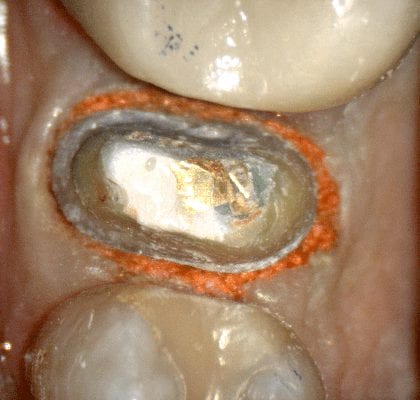

REMAINING TOOTH STRUCTURE AFTER REMOVAL OF PREVIOUS RESTORATION AND PREPARATION REFINEMENT

REMAINING TOOTH STRUCTURE AFTER PREVIOUS CROWN REMOVED AND THE PREPARATION REFINEMENT